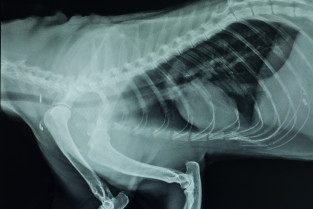

La radiographie reste un des principaux examens complémentaires de première intention en pneumologie.

L'espace d'une journée, nous vous proposons d'aborder les modalités d'une bonne réalisation et d'interprétation des radiographies du thorax. Nous nous attacherons également à analyser ensemble des images radiographiques normales et anormales du chat et du chien.

Un tour d'horizon des affections bronchopulmonaires, pleurales et extrapleurales et des autres méthodes d'imagerie utilisables sera envisagé grâce à un duo médecin/imageur.